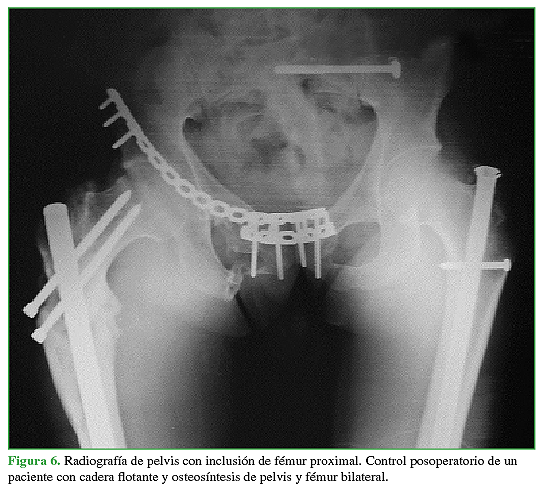

La fractura de fémur había sido tratada con clavos endomedulares en el 95,7% (n = 22) (Figura 6) y con placa y tornillos solo en el 4,3% (n = 1). La mediana de días de internación de esta población fue de 8 (rango 5-10). La mediana de la duración de los procedimientos fue de 247 min (rango 120-480) y la mediana de la pérdida hemática estimada durante la operación, de 500 ml (rango 300- 900).